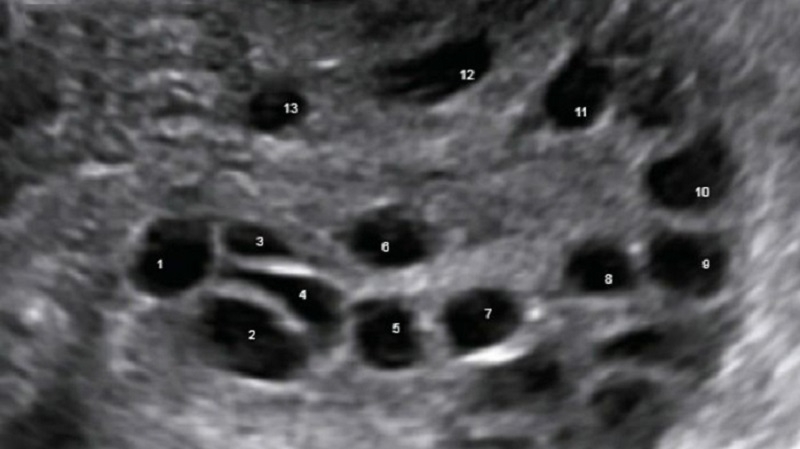

Buồng trứng đa nang

bệnh rối loạn nội tiết tố thường gặp ở phụ nữ trong độ tuổi sinh sản. Bệnh gây ra nhiều ảnh hưởng đến buồng trứng làm rối loạn kinh nguyệt, tăng tiết nội tiết tố androgen khiến hình thành nhiều u nang nhỏ bên trong buồng trứng. Sau 14 ngày trứng rụng, nội mạc tử cung được cắt bỏ. Nếu trứng không rụng mỗi tháng, lớp niêm mạc này không tách rời và dày lên, làm tăng nguy cơ ung thư nội mạc tử cung.

Thông qua việc siêu âm buồng trứng, bác sĩ có thể kiểm tra được tình trạng hiện tại của buồng trứng và độ dày của nội mạc tử cung, giúp bệnh nhân có những chẩn đoán chính xác và điều trị kịp thời.

Phụ nữ lo lắng nhất là bệnh buồng trứng đa nang làm rối loạn quá trình rụng trứng và giảm khả năng thụ thai. Nó đã được chứng minh là một trong những nguyên nhân gây vô sinh nữ.